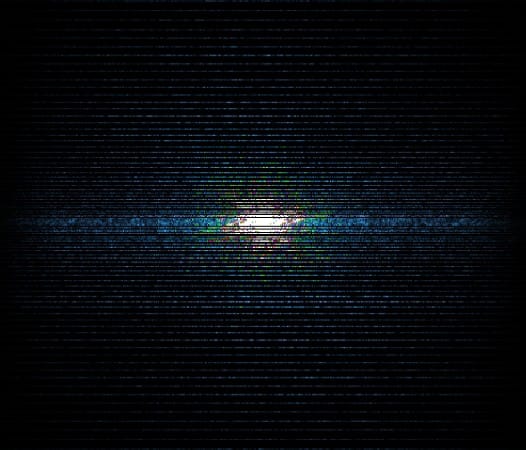

In the example below, only one fifth of the required MR radiofrequency signals is recorded. This results in a five times faster acquisition, with a subsampled k-space (top left) and inherent image artifacts after standard reconstruction (top right).

Basic compressed sensing principle